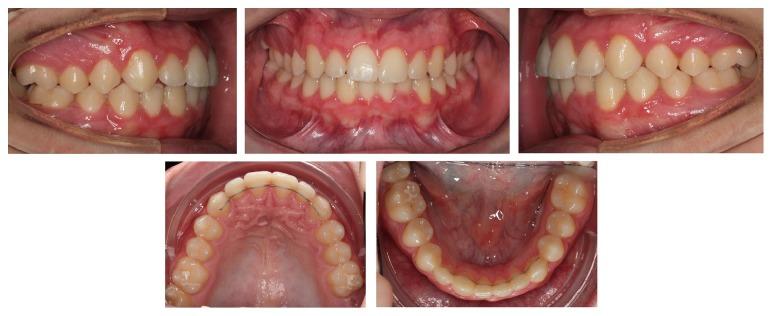

Bilateral mandibular tooth transposition is a relatively rare dental anomaly caused by distal migration of the mandibular lateral incisors and can be detected in the early mixed dentition by radiographic examination. Early diagnosis and interceptive intervention may reduce the risk of possible transposition between the mandibular canine and lateral incisor. This report illustrates the orthodontic management of bilateral mandibular canine-lateral incisor transposition. Correct positioning of the affected teeth was achieved on the left side while teeth on the right side were aligned in their transposed position. It demonstrates the outcome of good alignment of the teeth in the dental arch.

双侧下颌牙齿易位是一种相对罕见的牙齿异常,由下颌侧切牙向远中移位引起,可通过影像学检查在混合牙列早期发现。早期诊断和阻断性干预可能会降低下颌尖牙和侧切牙之间可能发生易位的风险。本报告阐述了双侧下颌尖牙-侧切牙易位的正畸治疗。左侧患牙实现了正确定位,而右侧牙齿则在其易位位置排齐。它展示了牙弓中牙齿良好排齐的效果。